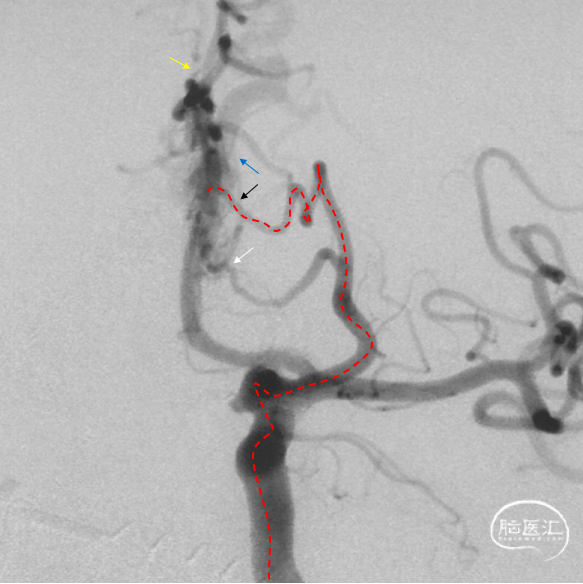

根据3D影像选择工作角度。

工作角度造影:黑色箭头为筛前动脉,白色箭头为筛后动脉,黄色箭头为镰前动脉,蓝色箭头为引流静脉起始部,红色箭头为视网膜中央动脉。拟通过眼动脉入路超选至筛前动脉进行栓塞。

Marathon微导管在Hybrid0.007微导丝导引下经左侧眼动脉超选至左侧筛前动脉,接近瘘口。

通过Marathon微导管超选造影,显示微导管楔入到靠近瘘口的动脉端。